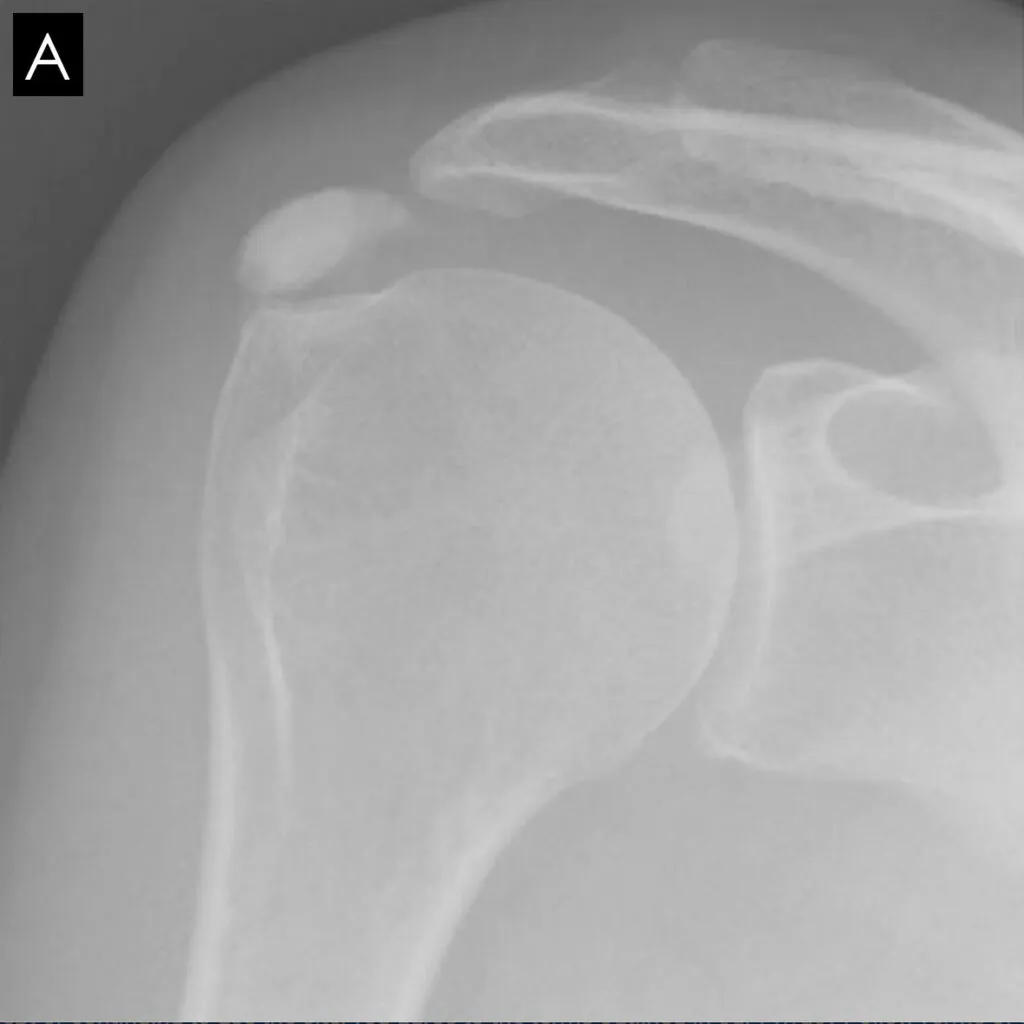

The radiographic morphology of the calcium deposits is the best indication of the stage.

It is dense and the edges are sharp in the formative and chronic phases.

In the resorption phase, the calcium deposits firstly become more translucent then the edges become blurred and heterogeneous.

X-rays are best to assess calcific tendonitis of the rotator cuff. The calcification can be located and the phase determined. In 80% of cases, it involves the supraspinatus tendon, in 15% of cases the infraspinatus tendon, and in 5% of cases the subscapularis tendon.